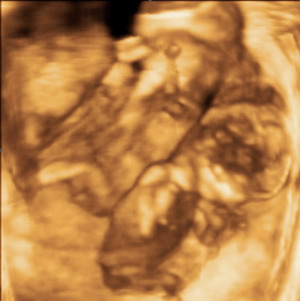

Andriska és Bernike